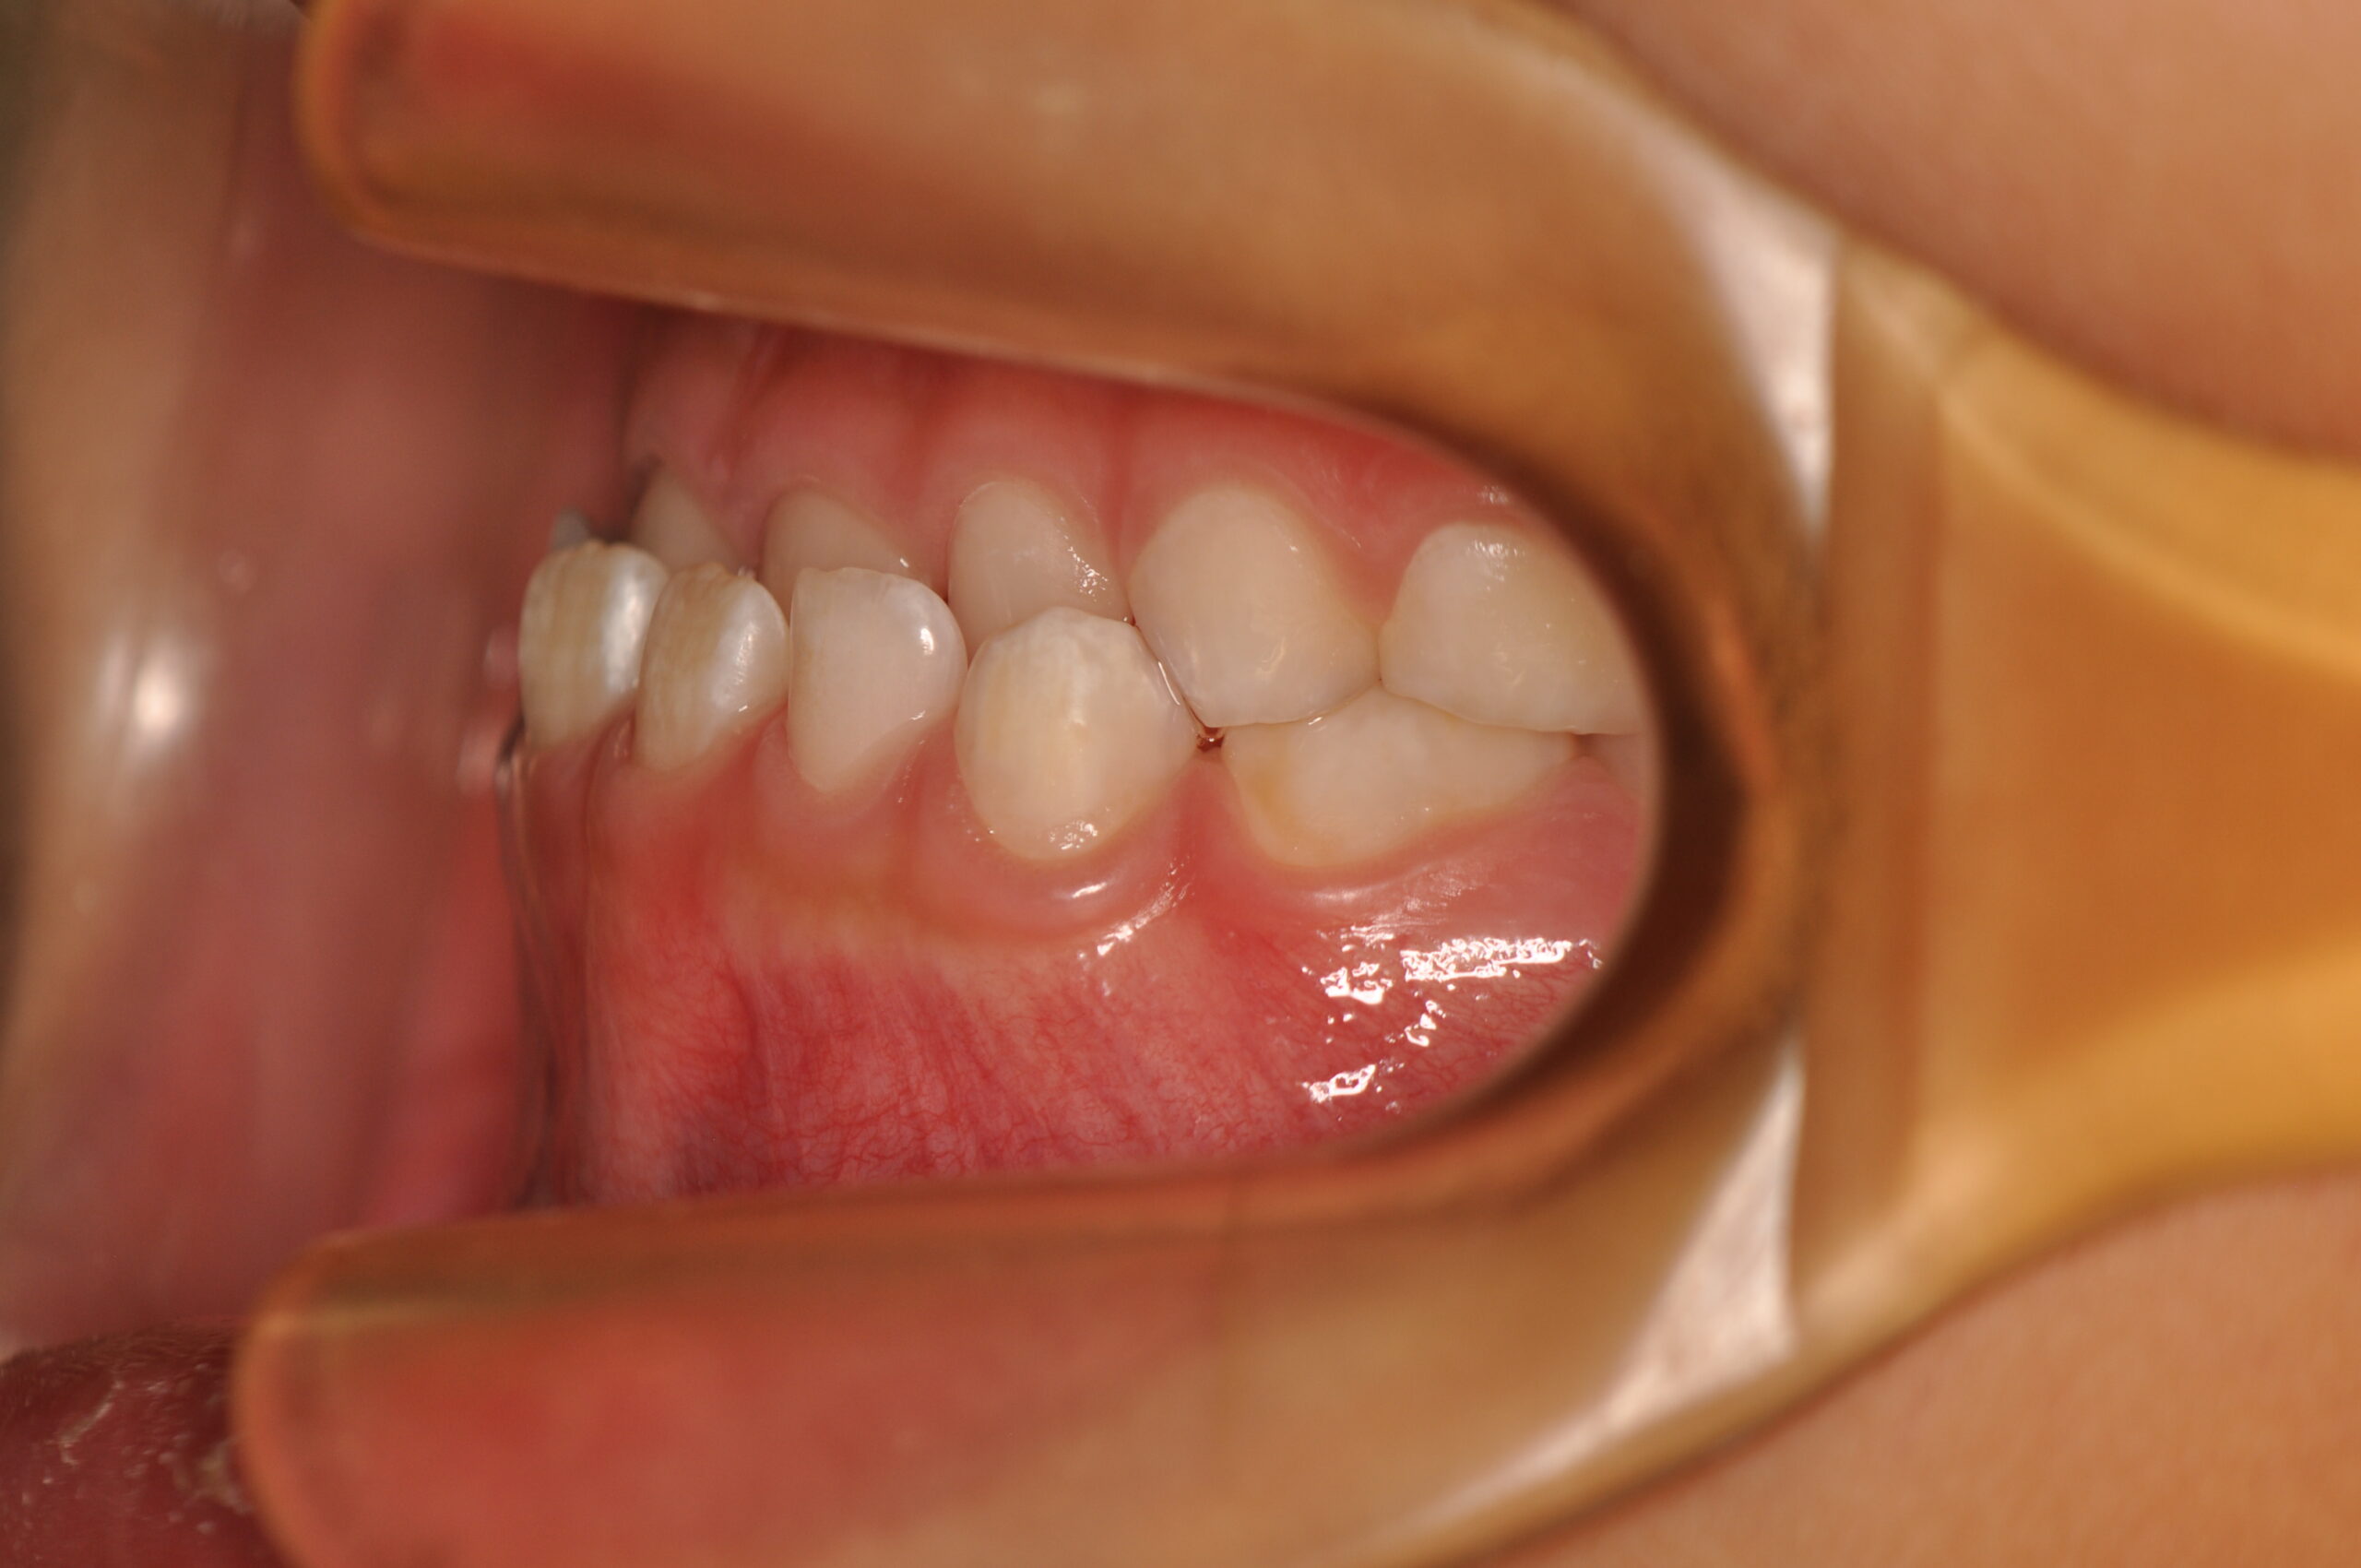

| 治療内容の詳細 | 初診時6歳の男性で、受け口を気にされ来院されました。 検査の結果、反対咬合を伴うアングルⅢ級不正咬合と診断しました。 治療としては、初期段階の治療として、機能的矯正装置で鼻呼吸の獲得と舌の位置や口唇の閉鎖といった筋機能習癖の改善を行い、上顎前方牽引装置を使用し上顎骨の前方方向への発育を誘導し、反対咬合の改善を行いました。 永久歯列に交換後、非抜歯の上、セルフライゲーションブラケット装置(デーモンシステム)で歯の配列と咬合関係の改善を行いました。 治療期間は、7年3ヶ月でした。 |